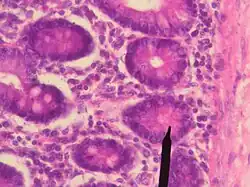

Бокаловидные клетки на разрезе ворсинки эпителия кишечника человека (помечены литерой e). Увеличение в 350 раз.

Энтероциты бокаловидные или бокаловидные клетки (лат. enterocytus caliciformis) — продуцирующие слизь клетки эпителия слизистой оболочки кишечника позвоночных животных и человека. В бокаловидных клетках накапливаются гранулы муциногена, которые, абсорбируя воду, набухают и превращаются в муцин (основной компонент слизи). При этом клетки обретают форму бокала, суженного у основания (где находится ядро) и округлой широкой в апикальной, верхней части. Затем набухшая верхняя часть бокаловидной клетки разрушается, слизь переходит в просвет органа, клетка приобретает призматическую форму и снова начинает накапливать муциноген. Кроме кишечника, бокаловидные клетки имеются в слизистой оболочке дыхательных путей, в конъюнктиве глаз, протоках поджелудочной и околоушной желёз.[5]